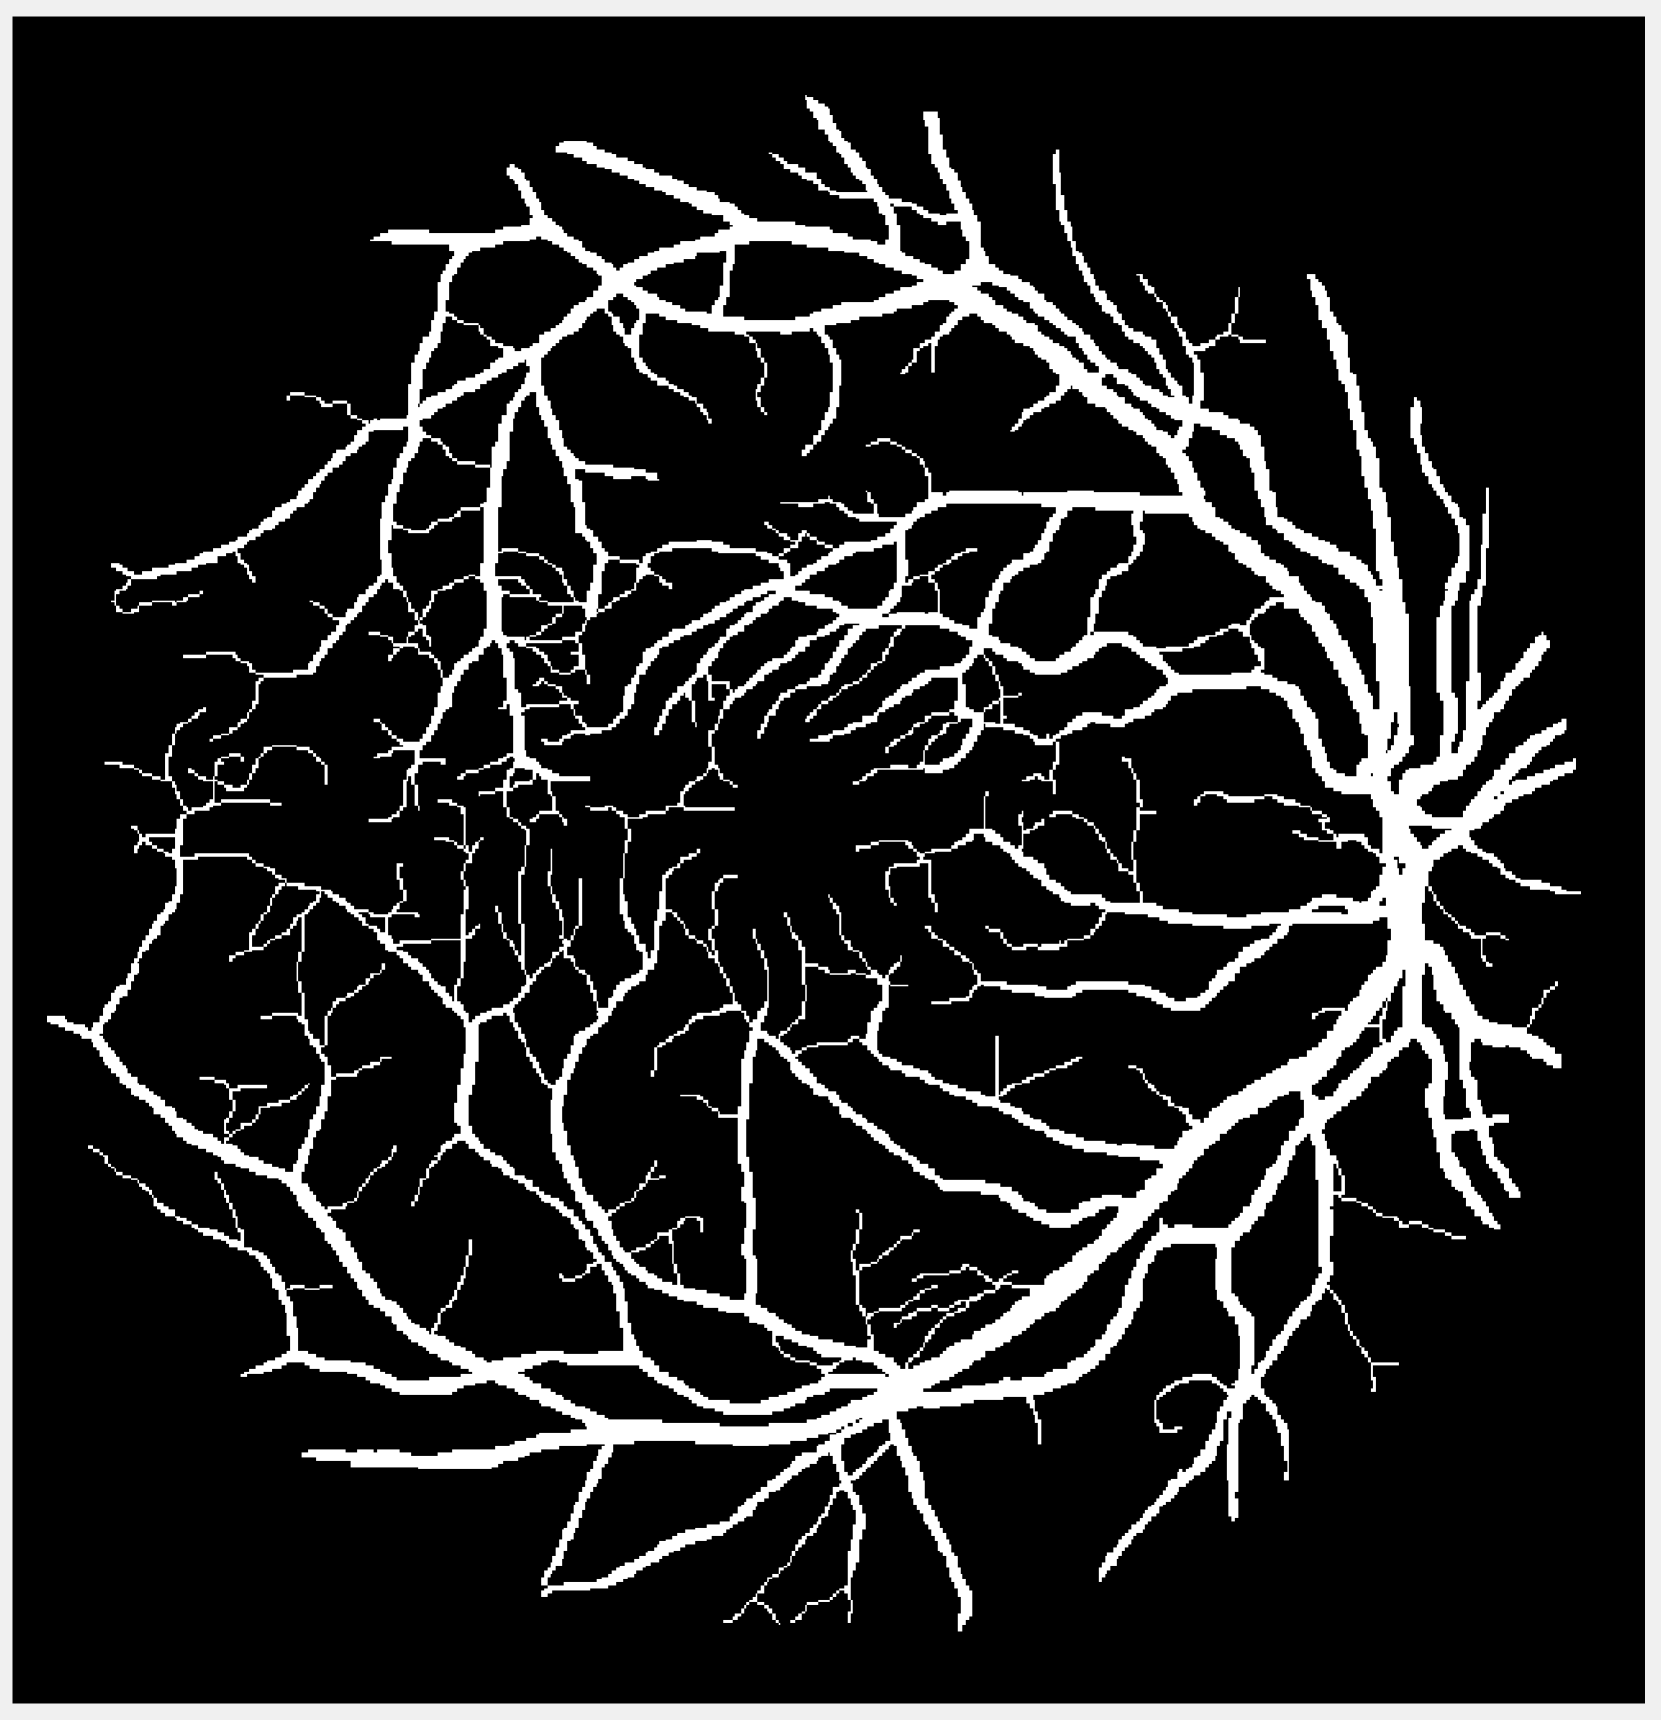

Refer to caption

Figure 3: Segmentation results of Figure 1(g) (after normalization) corrupted by Gaussian noise of mean 0 and variance 0.04. First row is CSF, second row is GM, and third row is WM.

Before applying the segmentation algorithms, the images in Figure 1 are normalized to [0,1]01[0,1][ 0 , 1 ] followed by Gaussian noise corruption. The retina vessel images are corrupted with Gaussian noise of mean 0 and variance 0.01. Table I reports the performances and times of the segmentation methods on the retina vessel images while Figure 2 shows some of their results. TTV (a=10,100)𝑎10100(a=10,100)( italic_a = 10 , 100 ) has the highest DICE and Jaccard similarity indices across the three images although requiring about 80 seconds to complete, thereby being slower than TV and TVp. The brain images are corrupted with Gaussian noise of mean 0 and variance 0.04. Table II reports the performances and times of the multiphase segmentation, while Figure 3 shows the segmentation results of Figure 1(g). By its DICE and Jaccard similarity indices, TTV (a=1)𝑎1(a=1)( italic_a = 1 ) is best at segmenting CSF across the four images while TTV (a=5,10)𝑎510(a=5,10)( italic_a = 5 , 10 ) remains competitive against AITV in segmenting GM and WM. On average, TTV (a=1,5)𝑎15(a=1,5)( italic_a = 1 , 5 ) is among the top two best-performing methods. Although it can be outperformed by AITV, it is at least three times faster. In Figure 3, we see that TTV (a=5)𝑎5(a=5)( italic_a = 5 ) is most effective in segmenting CSF, especially compared to TV and TVp. Moreover, comparable to TV and AITV, it is able to identify most of the GM and WM regions. Overall, using TTV, the proposed method is able to effectively identify narrow, thin regions such as the retina vessels and CSF.